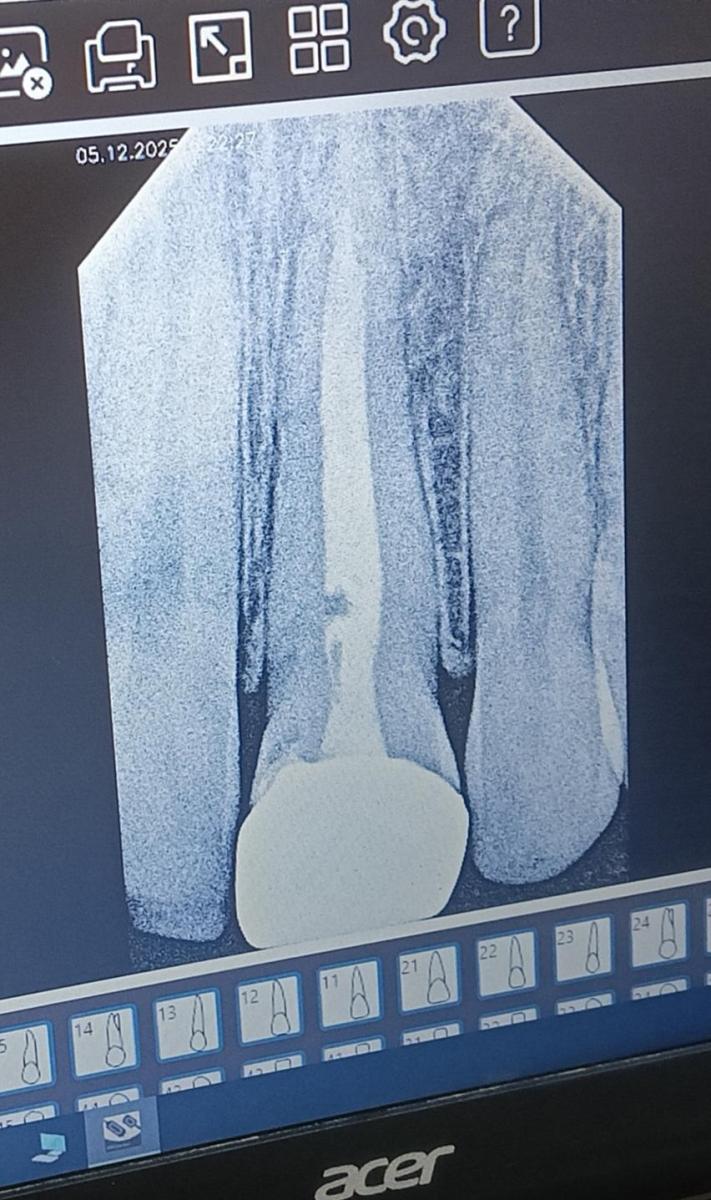

Каналы чистили 10 лет назад примерно, два года с небольшим поставили коронку и сейчас ощущается напряжение и боль под коронкой при надкусывании или лёгком надавливании. Сделала прицельный снимок, сказали, что всё хорошо, завтра поеду делать кт, чтобы увидеть всю картину. Что может быть и к чему готовиться?

Сделаете скрин с КТ, тогда может поговорим!